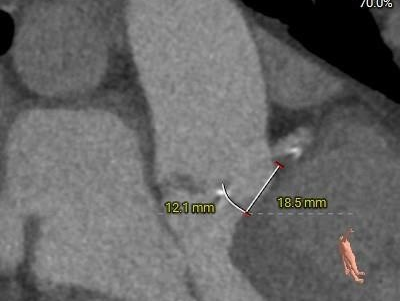

冠脉测量:

冠脉开口高度可,切线角度测量,左窦瓣叶长于左冠开口下缘。